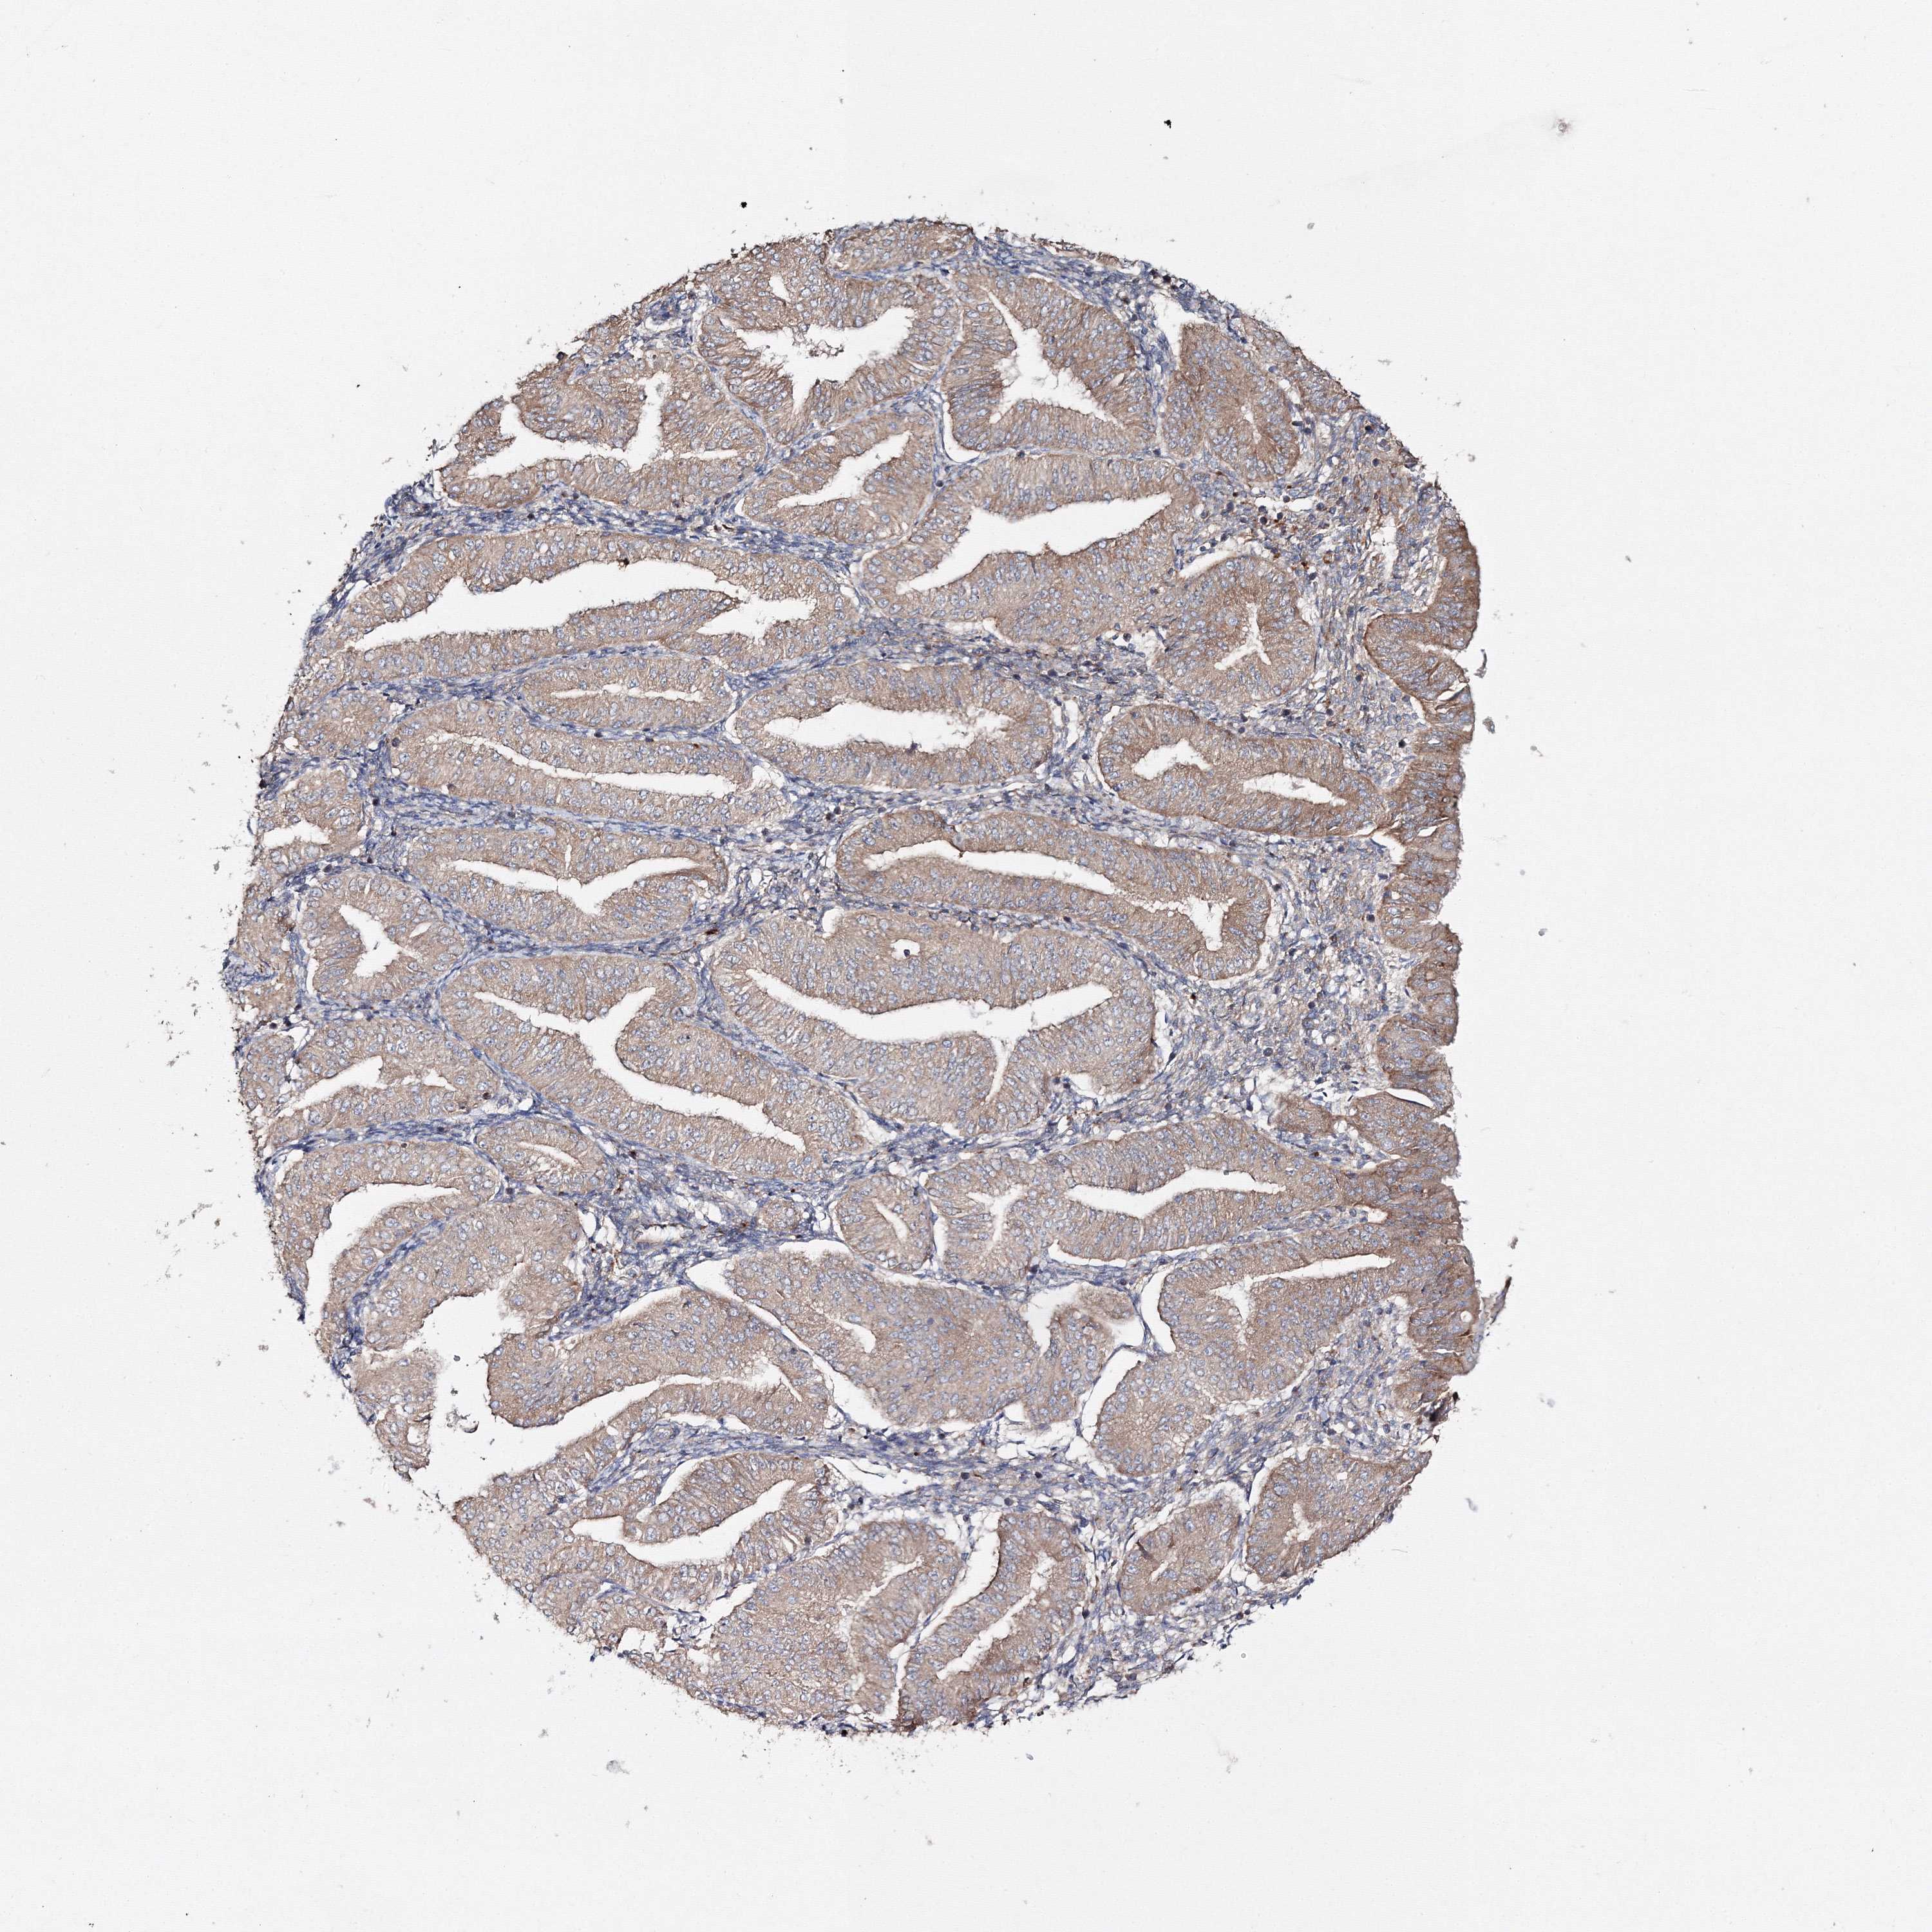

ENDOMETRIAL CANCER - Protein expressioni

A mouse-over function shows sample information and annotation data. Click on an image to view it in a full screen mode. Samples can be filtered based on level of antibody staining by selecting one or several of the following categories: high, medium, low and not detected. The assay and annotation is described here.

Note that samples used for immunohistochemistry by the Human Protein Atlas do not correspond to samples in the TCGA dataset.

Antibody stainingi

Antibody staining in the annotated cell types in the current human tissue is reported as not detected, low, medium, or high, based on conventional immunohistochemistry profiling in selected tissues. This score is based on the combination of the staining intensity and fraction of stained cells.

Each image is clickable and will lead to virtual microscopy that enables deeper exploration of all samples and also displays staining intensity scores, fraction scores and subcellular localization as well as patient and tissue information for each sample.

Antibody HPA037525

Antibody HPA037526

Staining

High

Medium

Low

Not detected

Intensity

Strong

Moderate

Weak

Negative

Quantity

>75%

75%-25%

<25%

None

Location

Nuclear

Cytoplasmic/membranous

Cytoplasmic/membranous,nuclear

Adenocarcinoma, NOS

Adenoma, NOS